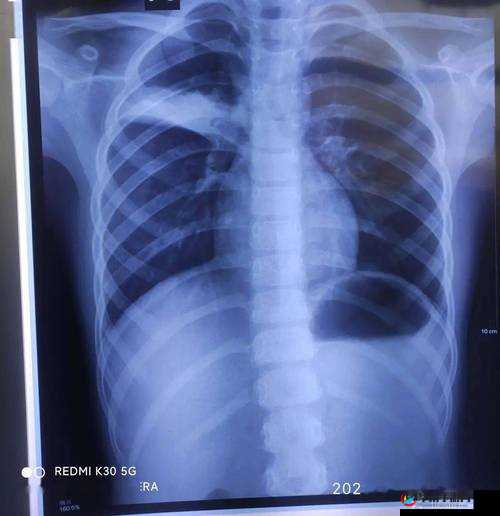

事件的起因源于一次看似普通的医疗检查。患者们在接受胸片检查时,意外发现自己的胸片竟然 100%曝光,这意味着他们的个人隐私在毫无防备的情况下被完全暴露。消息一经传出,舆论瞬间哗然。人们愤怒的不仅仅是隐私的泄露,更是对医疗体系安全性和规范性的深深质疑。